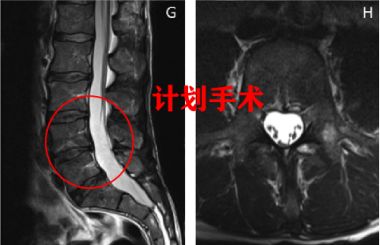

图二:LDH 患者 L4/5 发生自发性消退,MRI 显示 3 年后在 L5/S1 上出现新的突出。图源:DOI: 10.1155/2016/1538072